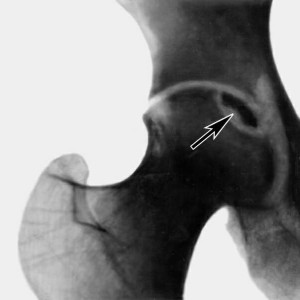

Следующим методом диагностики некроза является рентген. Его врачи используют чаще всего. Однако такое исследование не позволяет определить болезнь на ранних стадиях, когда лечение может быть максимально эффективным, когда проще всего остановить процесс омертвления или даже обратить его вспять. Только последние стадии могут быть определены с помощью рентгена.

Самым точным современным методом диагностики разрушения кости на ранних стадиях, является магнитно-резонансная томография. С ее помощью можно зафиксировать самые первые признаки омертвления кости. В настоящее время аппаратура для подобного исследования есть далеко не во всех клиниках и больницах. Да и не каждый человек может позволить себе такую дорогостоящую сложную диагностику.